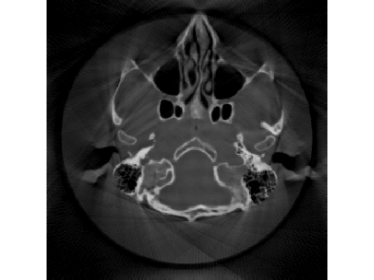

Finally, we apply the proposed method on a clinical head dataset. The data are acquired with a Siemens Artis zee angiographic C-arm system (Siemens Healthcare GmbH, Forchheim, Germany). In this experiment, we choose one slice of a 3D clinical head dataset as the ground truth image (Fig.9) and reproject it to simulate the acquired sinogram data in the fan-beam system with the following trajectory parameters: the source-to-isocenter distance is 750 mm and isocenter-to-detector distance is 450 mm. The angular step is 1 degree and the total scan range is 360 degrees. The equal-spaced detector length is 620 mm with the pixel length 111 mm.

The full projections are shown in Fig.10. When the detection range κ𝜅\kappa is limited, there could be saturation for the projection. In Fig.10 and Fig.10, observations for κ=0.6pmax𝜅0.6subscript𝑝\kappa=0.6p_{\max} and κ=0.4pmax𝜅0.4subscript𝑝\kappa=0.4p_{\max} are displayed, respectively. Our task is to recover the image from the saturated projections via M1bit-CS-ISD. The results are compared with FBP and SART, two standard CT reconduction frameworks. For FBP, we apply the modification given by [38] that utilizes water cylinder extrapolation to remedy missing projections caused by truncation or overexposure. For SART, one can remove those saturated projections when they are found, for which the ISD can be used as well. We denote this method as SART-ISD, of which the detection scheme is as the same as M1bit-CSR-ISD but SART is used as the reconstruction method.

Figure 9: Reconstruction results for the clinical data (κ=0.6pmax𝜅0.6subscript𝑝\kappa=0.6p_{\max}): (a) ground truth; (b) FBP-WCE; (c) SART-ISD; (d) M1bit-CSR-ISD.

For κ=0.6pmax𝜅0.6subscript𝑝\kappa=0.6p_{\max}, the reconstruction results of FBP-WCE and SART-ISD are given in Fig.9 and 9, respectively. As shown before, the traditional FBP method cannot handle the saturated data. With water cylinder extrapolation, the reconstruction quality has been improved but loss of clear patient boundaries still happens. The overall performance of SART-ISD is slightly better than FBP-WCE but capping artifact can be identified at the object border. Further improvement is obtained using the proposed M1Bit-CSR-ISD to acquire information from the saturated data. As shown in Fig.9, most of outer boundaries are nicely restored and streaking artifacts are effectively eliminated.